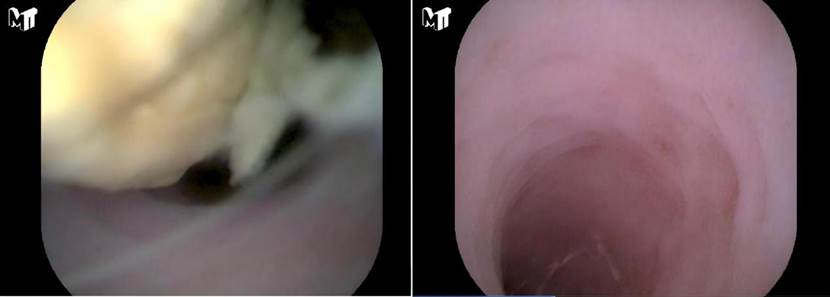

△术前阑尾粪石(图左)与治疗后影像(图右)

该患者因转移性右下腹痛来诊,经检查确诊为急性单纯性阑尾炎,原本计划接受传统腹腔镜手术。然而,在了解到一项名为“经内镜逆行阑尾炎治疗术(ERAT)”的新型微创技术后,患者表示对微创治疗有强烈意愿。经多学科会诊、消化内科团队详细评估后,该患者病情符合ERAT适应症。在与患者及家属充分沟通并取得同意后,医疗团队将其转入消化内科,成功实施了ERAT。术中经结肠镜精准找到阑尾开口,进行冲洗并取出粪石,引流出浑浊脓液,阑尾腔瞬间减压,患者全程麻醉,体验良好。术后腹痛迅速缓解,复查炎症指标明显下降,在术后次日患者腹痛症状就完全消失,顺利康复出院。